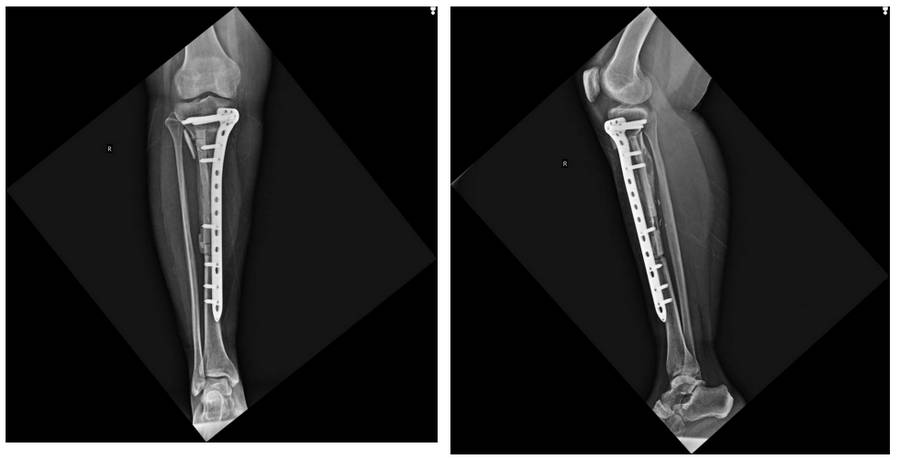

Ameliyat Sonrası: Röntgende geri kazanılan kemik ve fibulanın anatomik plak ile fiksasyonu görülmekte